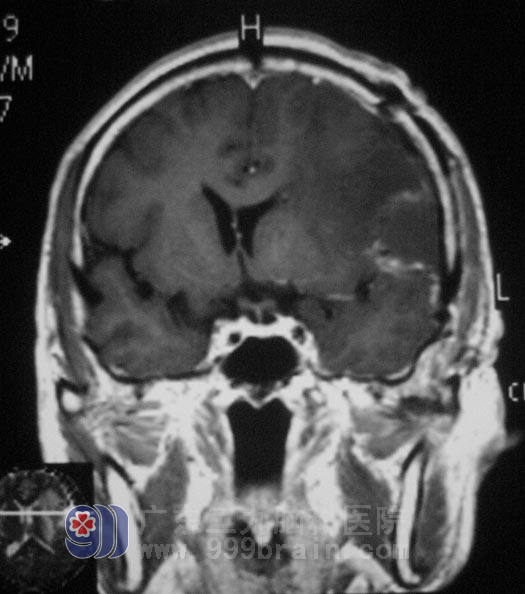

住进广东三九脑科医院综合神经外科后,头颅核磁共振结果提示:左侧额颞叶交界处占位病灶,大小约27mm×36.4mm×41.3mm,初步考虑恶性肿瘤,胶质母细胞瘤可能性大,不排除单发转移瘤;而且伴有大脑镰下疝形成、脑白质散在脱髓鞘灶。

余老伯的肿瘤压迫症状明显,精神食欲差,右下肢肢体乏力,日常生活需要家人协助,经检查排除转移瘤的可能。在完善手术相关准备后,由鲁明主任主刀,在全麻下行“左侧额颞叶肿瘤切除术”,术中见肿瘤呈鱼肉样,额下回局部脑组织水肿明显,肿瘤质地较韧。在显微镜下沿边界全切肿瘤,术后CT显示:余先生颅内压力和脑水肿情况均较术前明显缓解,头痛症状也有所好转。手术后,余先生精神食欲明显好转,脸上的笑容和话语也多了,已经能自行下床活动。术后经病理证实为:(左额颞叶)胶质肉瘤,WHO IV级。余先生还要接受后续的放化疗。